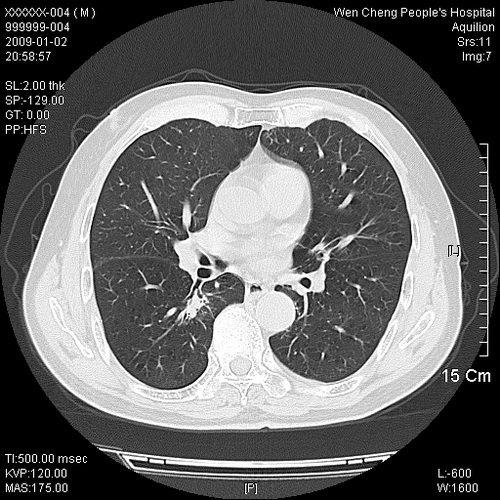

男性,73岁,有慢支病史,肿瘤系列标志物检验正常,血沉及血常规正常

右肺下叶背段小片状 磨玻璃样模糊影,内见血管及含气支气管像,支气管管壁增厚。考虑:慢性炎症!

右肺下叶背段小片状 实性与磨玻璃样影,内见血管及含气支气管像,支气管管壁增厚,边缘见长毛刺影。考虑:慢性炎症或肿瘤!建议抗炎治疗复查,密切观察随访!

右肺下叶片团状影内见扩张的含气支气管和支气管管壁增厚,其周有磨玻璃样模糊影和长毛刺。考虑慢性炎症可能性大。

2、右肺下叶片团状影内见扩张的含气支气管和支气管管壁增厚,其周有磨玻璃样模糊影和长毛刺。考虑周围型肺ca可能,结核不排。

高度提示细支气管肺泡癌,建议抗炎治疗半月观察病灶变化,如无明显改变,建议立即手术治疗.